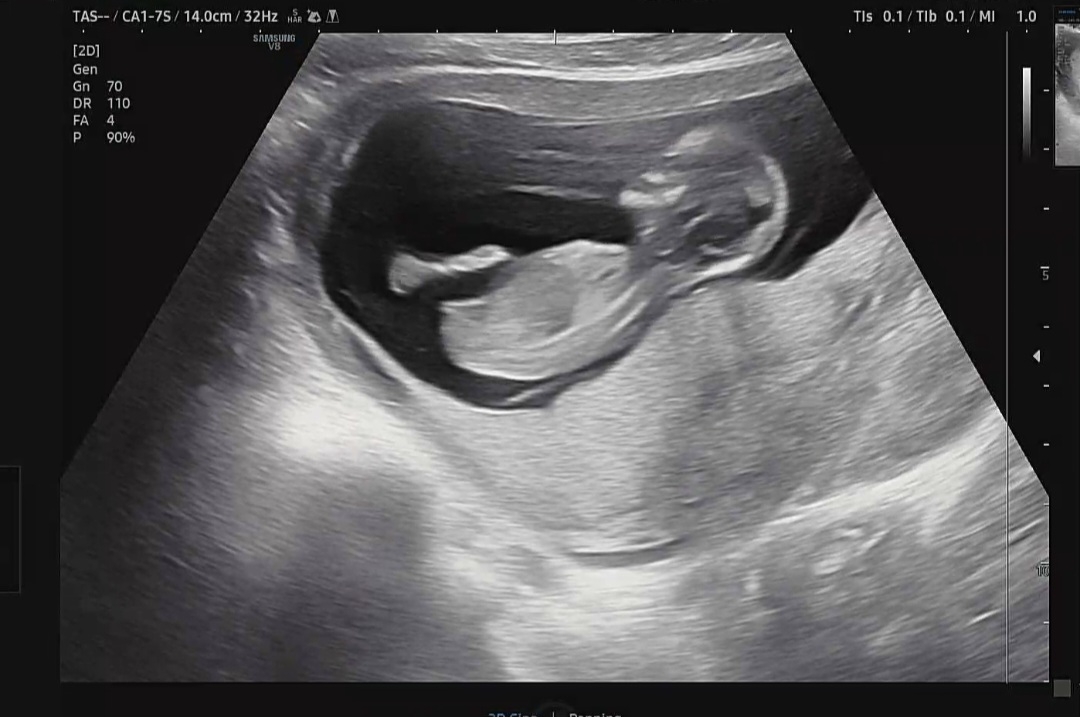

12주차 각도법 궁금해요! 보이실까요?

돌기가 보이는게 맞나 모르겠네요 각도법 유추 가능한가요?